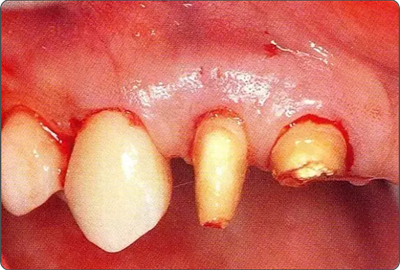

深牙周袋的治療

圖10-2  x片顯示的遠(yuǎn)中部有垂直性骨缺損。